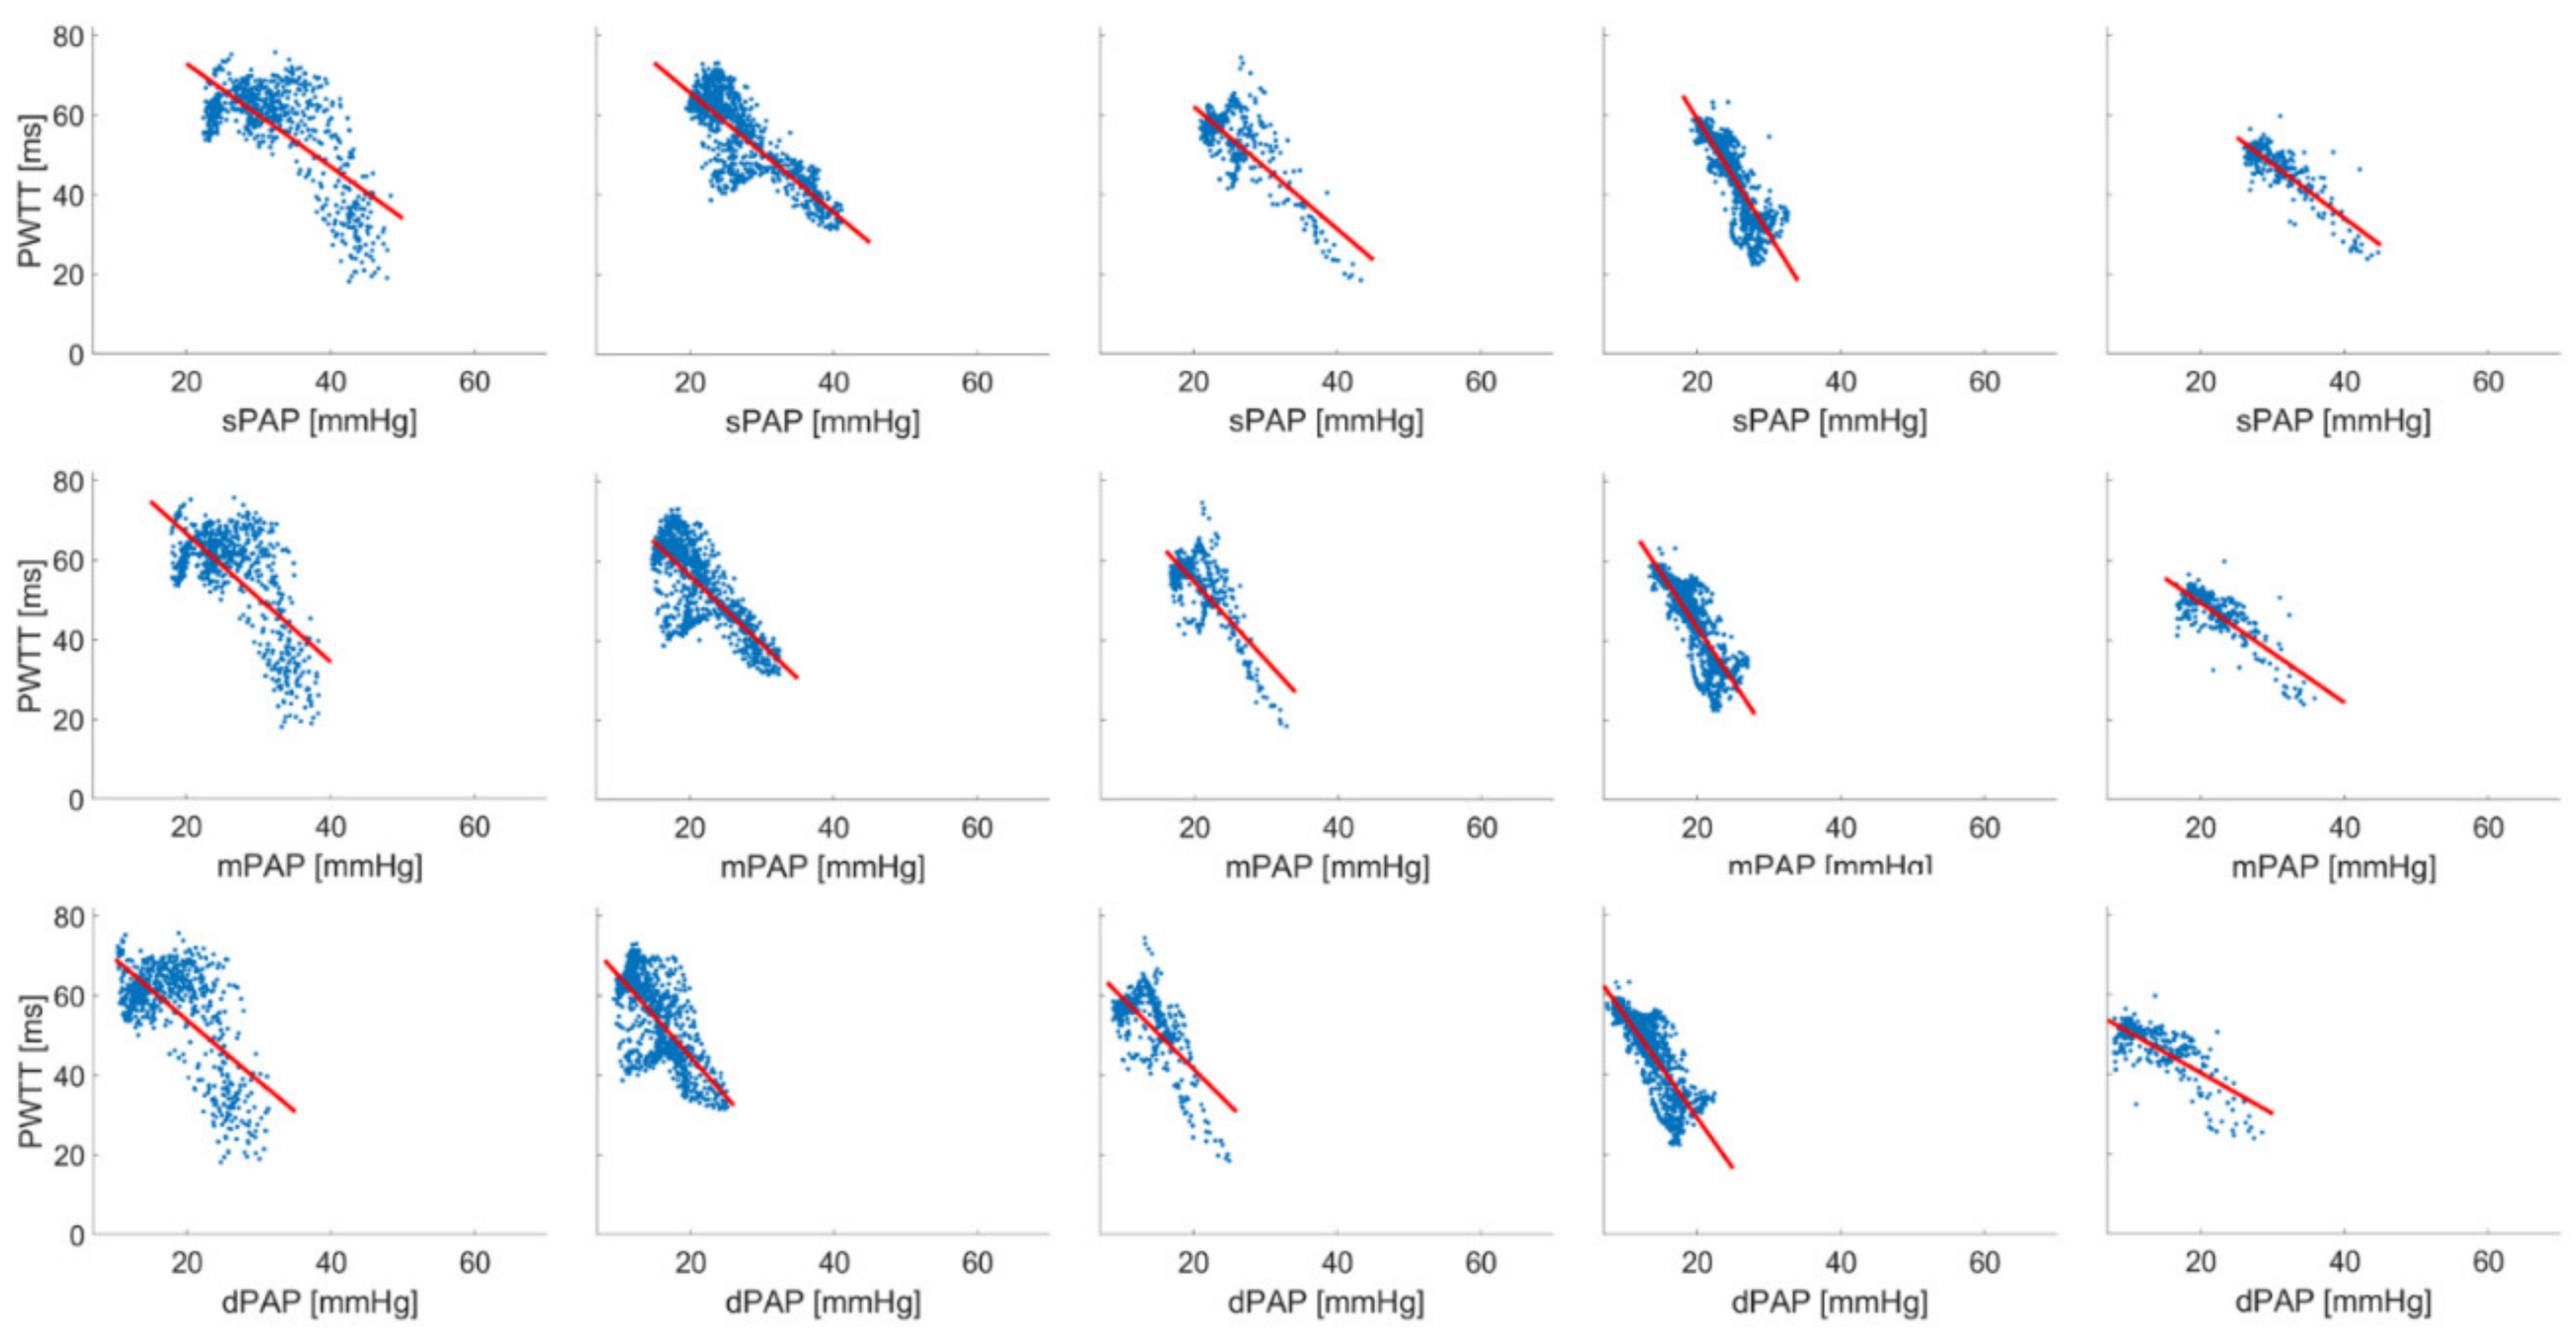

| A | sPAP | mPAP | dPAP | ||||||||||

| Pig | n | Linear Regression | r2 | F | p | Linear Regression | r2 | F | p | Linear Regression | r2 | F | p |

| 1 | 1611 | PWTT = 70.945 − (0.481 * sPAP) | 0.356 | 888.151 | <0.001 | PWTT = 83.645 − (0.969 * mPAP) | 0.499 | 1601.15 | <0.001 | PWTT = 49.662 − (0.112 * dPAP) | 0.00885 | 14.364 | <0.001 |

| 2 | 686 | PWTT = 98.938 − (1.298 * sPAP) | 0.502 | 689.041 | <0.001 | PWTT = 99.054 − (1.616 * mPAP) | 0.466 | 596.726 | <0.001 | PWTT = 84.597 − (1.537 * dPAP) | 0.430 | 517.007 | <0.001 |

| 3 | 333 | PWTT = 42.133 − (0.646 * sPAP) | 0.547 | 400.226 | <0.001 | PWTT = 44.194 − (0.917 * mPAP) | 0.534 | 379.604 | <0.001 | PWTT = 37.053 − (0.967 * dPAP) | 0.542 | 391.071 | <0.001 |

| 4 | 377 | PWTT = 46.632 − (0.683 * sPAP) | 0.399 | 248.757 | <0.001 | PWTT = 44.595 − (0.815 * mPAP) | 0.210 | 90.716 | <0.001 | PWTT = 43.850 − (1.239 * dPAP) | 0.245 | 121.935 | <0.001 |

| 5 | 426 | PWTT = 81.659 − (2.047 * sPAP) | 0.649 | 783.579 | <0.001 | PWTT = 62.936 − (1.719 * mPAP) | 0.597 | 628.24 | <0.001 | PWTT = 46.610 − (1.243 * dPAP) | 0.447 | 342.462 | <0.001 |

| 6 | 440 | PWTT = 63.723 − (0.972 * sPAP) | 0.765 | 1422.27 | <0.001 | PWTT = 62.645 − (1.129 * mPAP) | 0.686 | 955.157 | <0.001 | PWTT = 58.002 − (1.188 * dPAP) | 0.628 | 738.206 | <0.001 |

| B | sPAP * | mPAP | dPAP | ||||||||||

| Pig | n | Linear Regression | r2 | F | p | Linear Regression | r2 | F | p | Linear Regression | r2 | F | p |

| 1 | 686 | PWTT = 98.938 − (1.298 * sPAP) | 0.502 | 689.041 | <0.001 | PWTT = 99.054 − (1.616 * mPAP) | 0.466 | 596.726 | <0.001 | PWTT = 84.597 − (1.537 * dPAP) | 0.430 | 517.007 | <0.001 |

| 2 | 1022 | PWTT = 95.676 − (1.501 * sPAP) | 0.671 | 2083.98 | <0.001 | PWTT = 90.743 − (1.719 * mPAP) | 0.598 | 1518.03 | <0.001 | PWTT = 85.160 − (2.027 * dPAP) | 0.503 | 1030.82 | <0.001 |

| 3 | 444 | PWTT = 93.021 − (1.542 * sPAP) | 0.597 | 653.743 | <0.001 | PWTT = 93.907 − (1.967 * mPAP) | 0.547 | 534.506 | <0.001 | PWTT = 77.779 − (1.806 * dPAP) | 0.467 | 386.649 | <0.001 |

| 4 | 1040 | PWTT = 117.075 − (2.902 * sPAP) | 0.750 | 3114.64 | <0.001 | PWTT = 97.682 − (2.717 * mPAP) | 0.730 | 2804.00 | <0.001 | PWTT = 80.169 − (2.548 * dPAP) | 0.709 | 2531.34 | <0.001 |

| 5 | 290 | PWTT = 88.233 − (1.354 * sPAP) | 0.716 | 725.429 | <0.001 | PWTT = 74.310 − (1.249 * mPAP) | 0.652 | 539.333 | <0.001 | PWTT = 60.839 − (1.024 * dPAP) | 0.551 | 354.094 | <0.001 |